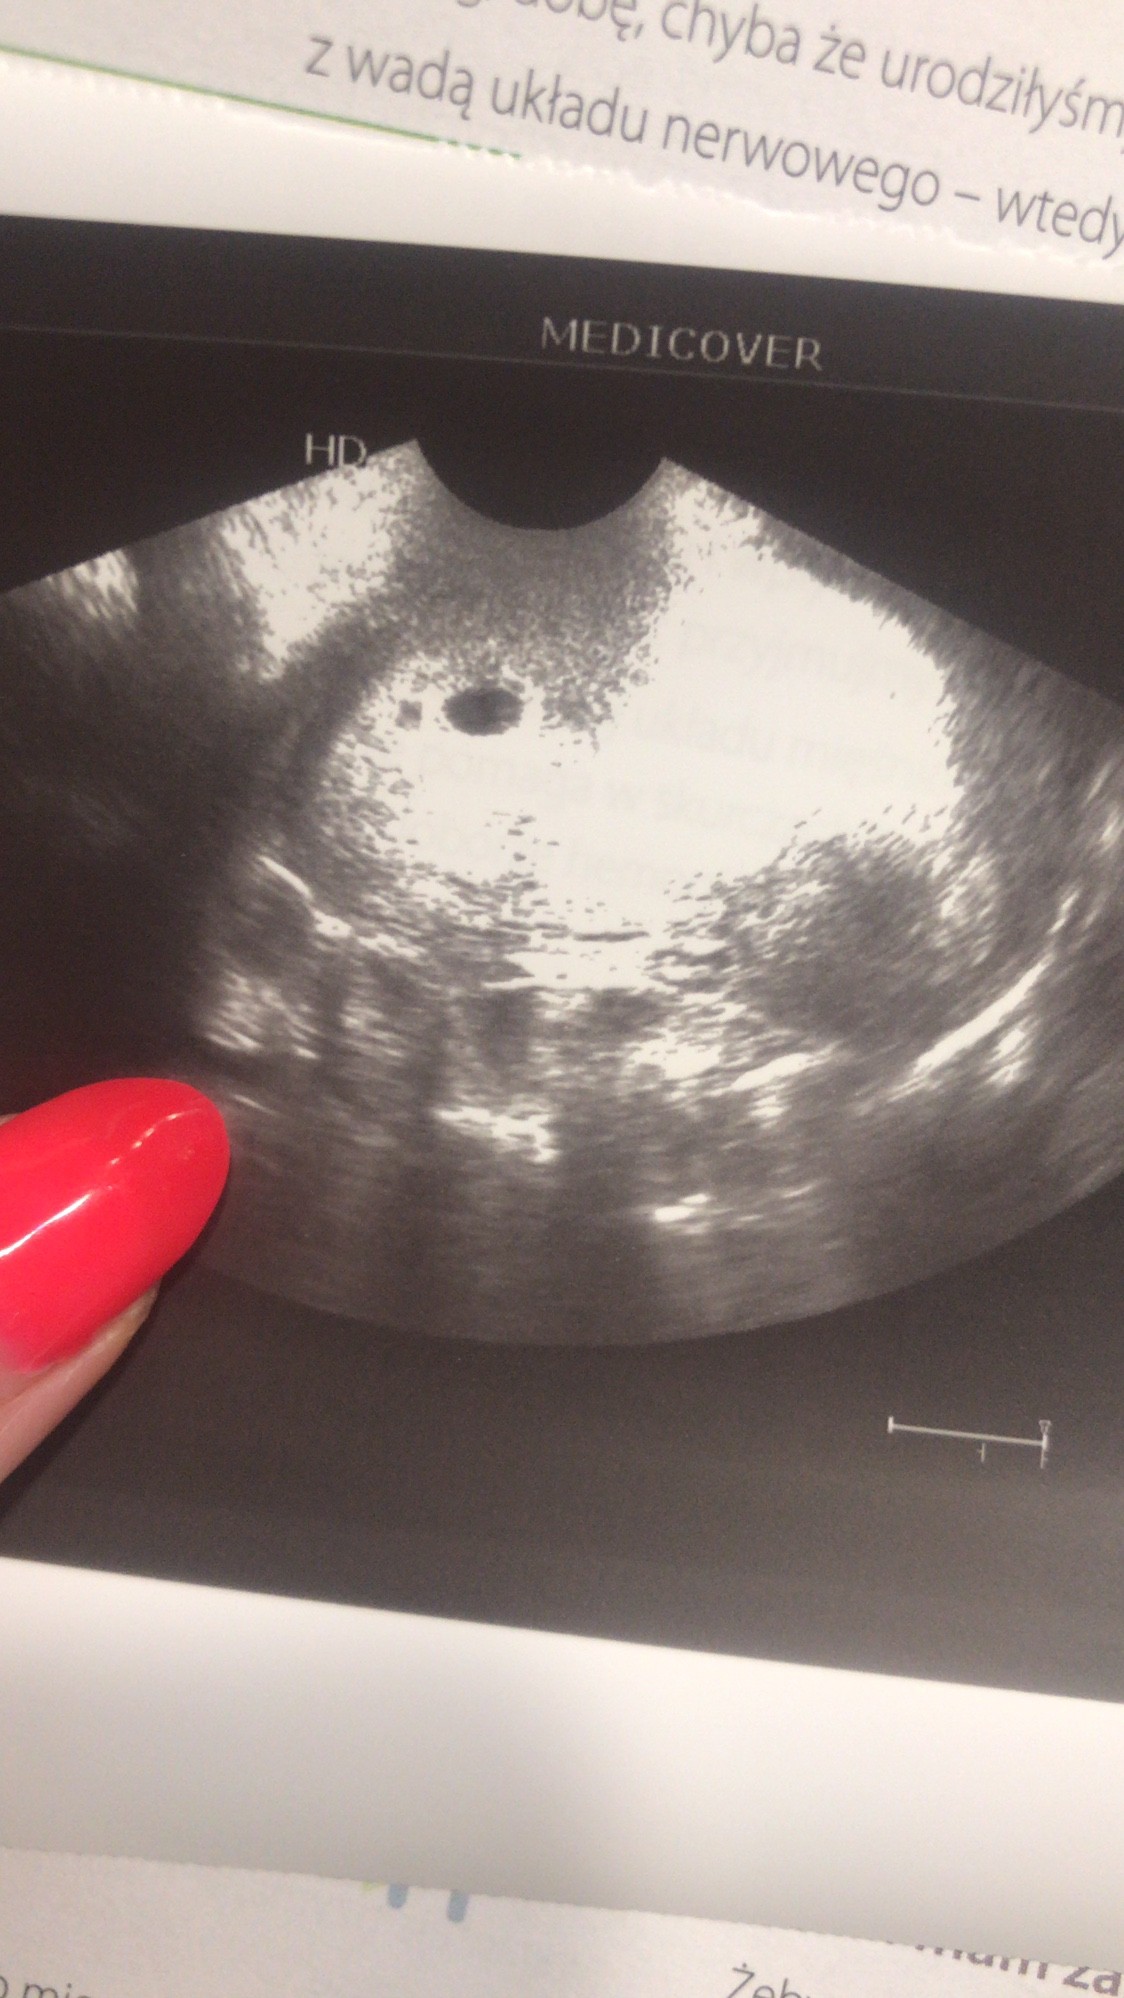

11.07 miałam @test ciążowy wychodził mi pozytywny już w 24dc. Zrobiłam bete: 26dc 95, 28dc 294, 31dc 1148 (godz 18.00), 33dc 2250 (godz 8:30). Wczoraj byłam u lekarza, według om byl to 5tc+5 a z usg 5tc+2. Widoczny był tylko pęcherzyka i zmartwilam się że nic więcej nie zobaczył mimo że owulacje miałam w 13/14dc. Mam przyjść za tydzień, ale trochę się podlamalam. Czy ktoś miał podobna sytuacje? Czy mimo wzrastającej wcześniej bety ich może się teraz ciąża nie rozwijać prawidłowo czy to za wcześnie na zarodek?